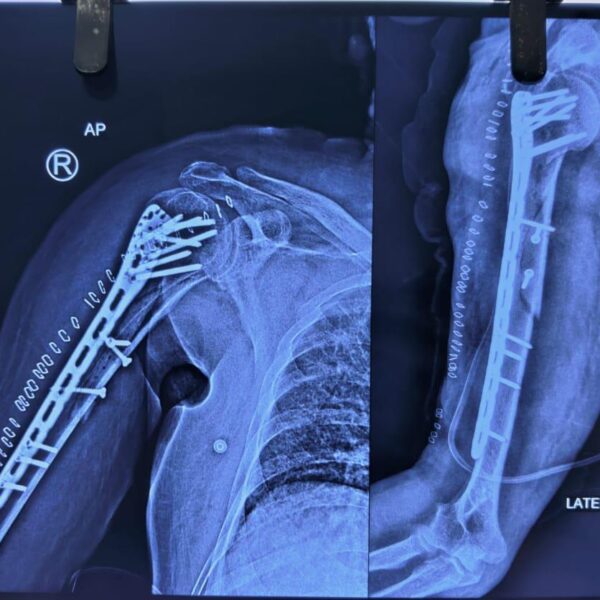

Moments That Mark Meaningful Recovery

Witness real patient transformations at The Ortho Clinic through images that reflect successful treatments and restored mobility.